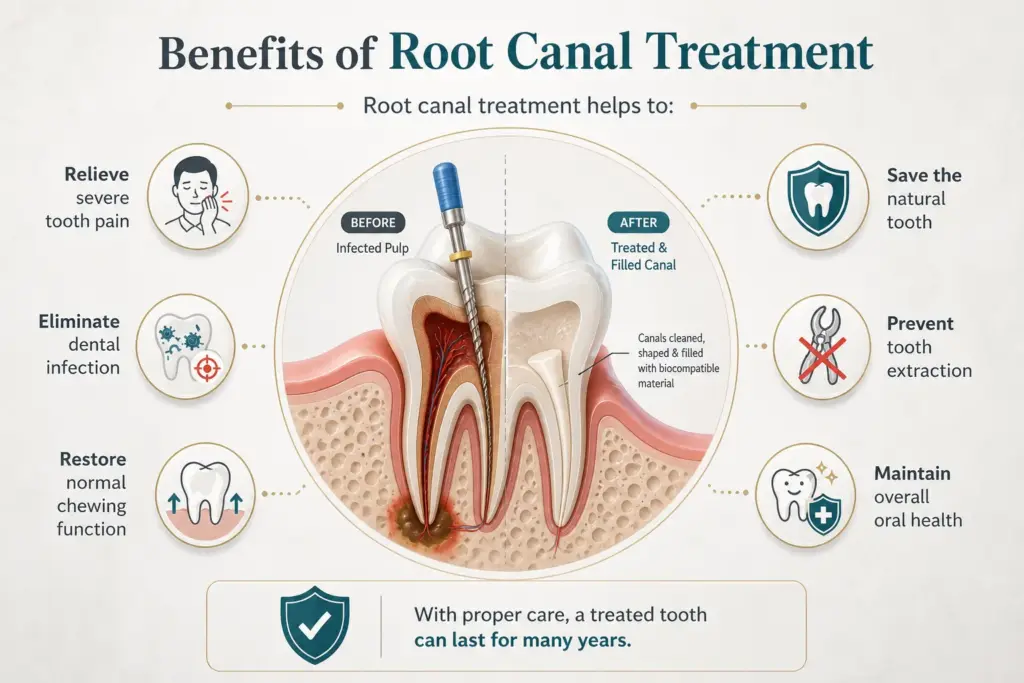

Benefits of Root Canal Treatment

Root canal treatment helps to:

- Relieve severe tooth pain

- Eliminate dental infection

- Save the natural tooth

- Restore normal chewing function

- Prevent tooth extraction

- Maintain overall oral health

With proper care, a treated tooth can last for many years.